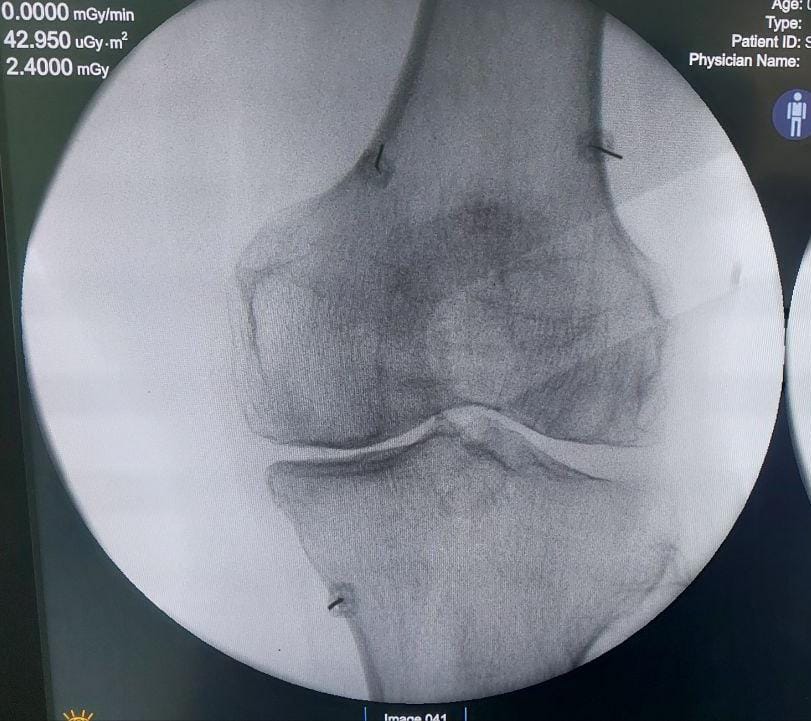

Struggling with chronic pain? Get advanced, personalised pain management from Dr. Manish De, one of Kolkata’s leading pain specialists. From knee pain, heel pain, low back pain, frozen shoulder, migraines, cancer pain to post-TKR persistent pain—Dr. De offers safe, evidence-based treatments across multiple locations: